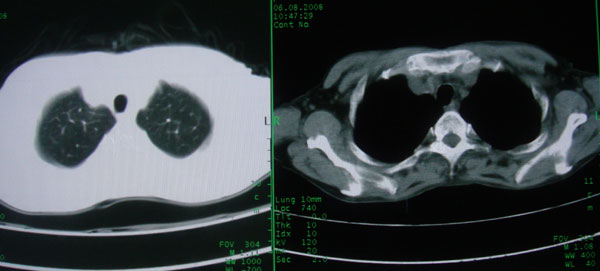

考虑支气管扩张并感染

1慢支伴感染;右下肺周围型肺癌。

1\\慢支并感染

2\\浸润型肺结核

本例应该是“慢性疾病并发多种合并症”即:慢支并感染并支气管扩张征!结合病灶分布 形态分析,不除外合并“继发性肺结核”!

慢性支气管炎伴支气管扩张\\感染

肺间质性改变 支气管扩张合并感染

慢性支气管炎伴全小型肺气肿、支气管扩张、感染、间质纤维化。

多考虑支气管扩张并感染,双下肺继发性肺结核不除外

周围型肺癌征象不明显,应不予首先考虑